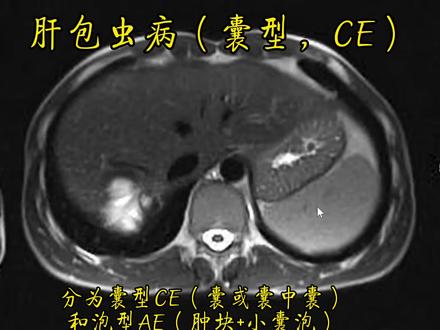

什么是包虫病呢?在高原地区我们看到很多人就是在做肝脏 ct 的时候提示肝包虫病,那么到底什么是包虫病呢?包虫病,它学名又叫做脊球幼病,是脊球掏虫的幼虫寄生在人兽体内引起的一种寄生虫病, 俗称为包虫病、包虫病,它是一种古老的人畜共患病,人、牛、羊等动物都可以患此类病。病原体它是一种很小的掏虫, 叫几球掏虫,一般长约二到七毫米,宽一毫米。仁和家畜最初吃了掏虫的虫卵,虫卵在我们的肝脏或肺里边等器官,它可以发育成为了包囊,从而就就形成了这个包虫病。